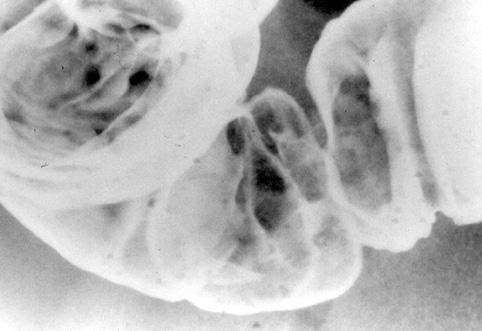

A case of cap polyposis in the rectum and sigmoid colon.

[ Image ID:9925 ]

Inflammatory or ulcerative disease / lesions/Others

Large intestine(Colon)/Sigmoid colon

X-ray

10 - 14